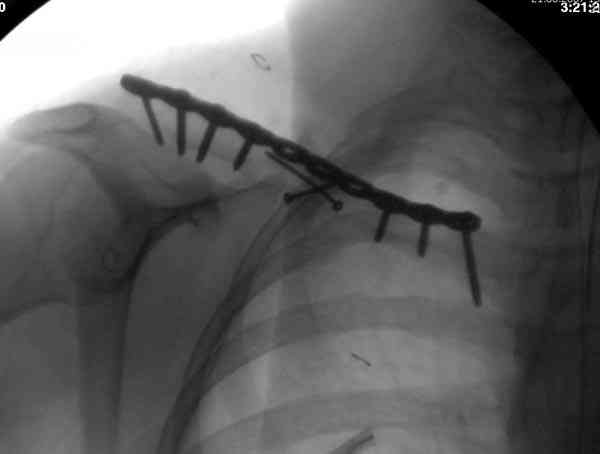

Второй случай тоже недавно оперирован по поводу

ложного сустава, в марте травма, через 4.5 половиной

операция..

Описанный случай это больная моего партнера, мы недавно случай разбирали на нашей конференции (Morbidity and Mortality Conference аналог клинического разбора)

Выставлен как пример, к чему может привести

неудачно выбранный фиксатор.